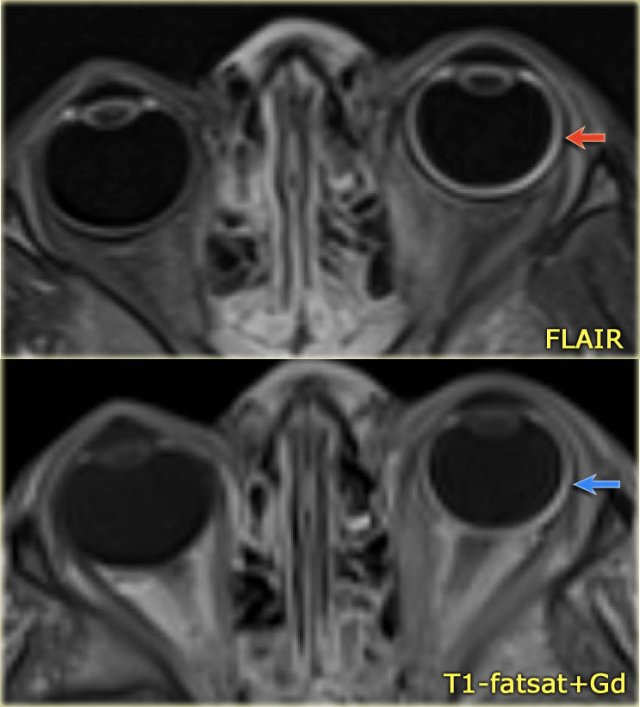

Eye abnormalities in a 4-year-old boy with Sturge-Weber syndrome.

Notice FLAIR-hyperintensity (red arrow) and excessive enhancement of the wall of the left globe (blue arrow) consistent with a diffuse choroidal hemangioma.